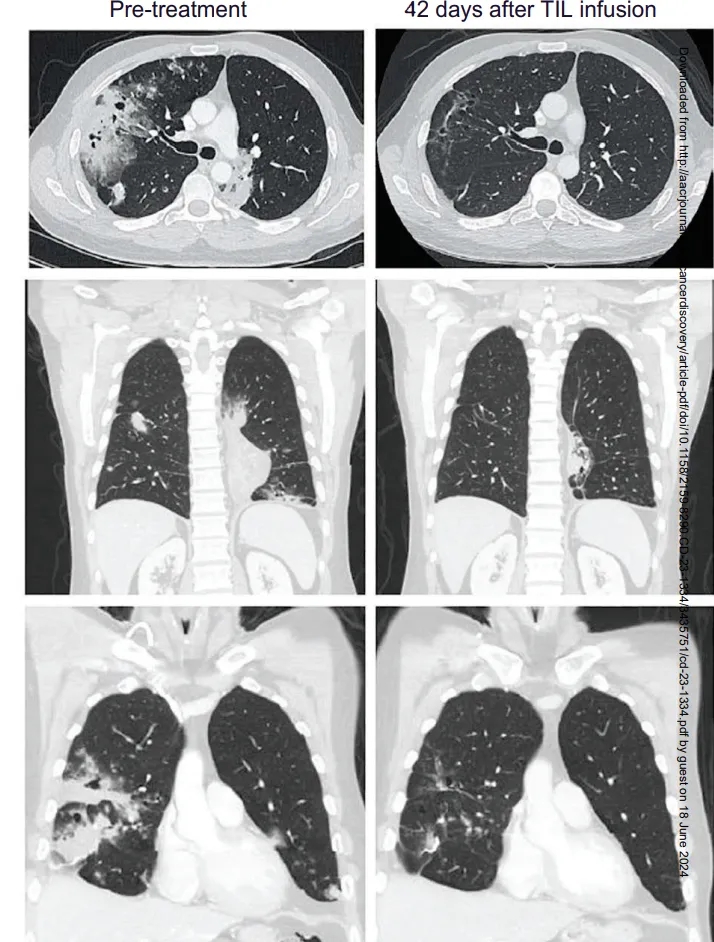

此外,国际顶级期刊《癌症探索》报道了lifileucel(Amtagvi)TIL疗法的振奋案例:41岁M先生确诊晚期粘液性肺腺癌(KRASG12D突变、PD-L10%),经卡铂+紫杉醇+派姆单抗三线治疗进展后接受TIL治疗,6周病灶显著缩小,12周肿瘤缩小81%!